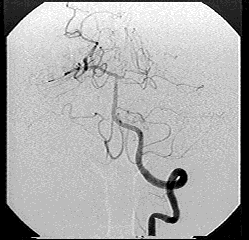

2.4 Operations on pixels

Arithmetic operations can be applied on pixels p and q on the same position in 2 images of the same size; examples are: addition, subtraction, multiplication and division of pixel values. A practical application of + and /  is the averaging of images to diminish noise. Subtraction is used for Digital Subtraction Angiography (DSA) in medical applications where sensing recordings are made before and after the injection of a contrasting liquid in the veins. Subtraction of the images will give a good impression of the circulation in the veins or possible obstruction thereof.

Click here for a series of DSA images (animated GIF)

see Angiography for more information.